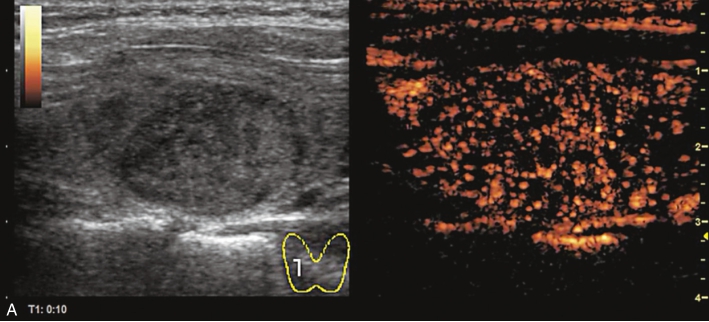

甲状腺右叶中部结节超声造影后早于周围组织开始,自周边向中心逐渐增强,达峰时呈不均匀等增强,增强范围较常规超声增大,周边可见不规则环状高增强,结节前方甲状腺被膜连续性中断,之后消退呈明显低增强,见图1-9-8。

图1-9-8 甲状腺髓样癌超声造影图

A.动脉早期;B.达峰时;C.增强晚期

甲状腺右叶中部低回声结节伴有多发钙化,边界不清,形态不规则,血流丰富;超声造影后呈不均匀低增强,周边可见不规则环状高增强结节增强范围较常规超声增大,结节前方甲状腺被膜连续性中断,上述特征均提示恶性。

甲状腺髓样癌超声表现多样,微小结节时与乳头状癌表现类似(特别是伴有钙化时),结节较大时与腺瘤表现类似,内部液化与丰富的血流信号是其鉴别点,边缘分叶状也是其常见的表现类型,超声造影时结节可呈高增强、等增强及稍低增强,周边不规则环状增强及范围扩大可进行良恶性鉴别,本例结节前方甲状腺被膜连续性中断,提示甲状腺前被膜受侵,得到术后病理证实。实验室检查中降钙素、CEA升高对于确诊具有重要意义。